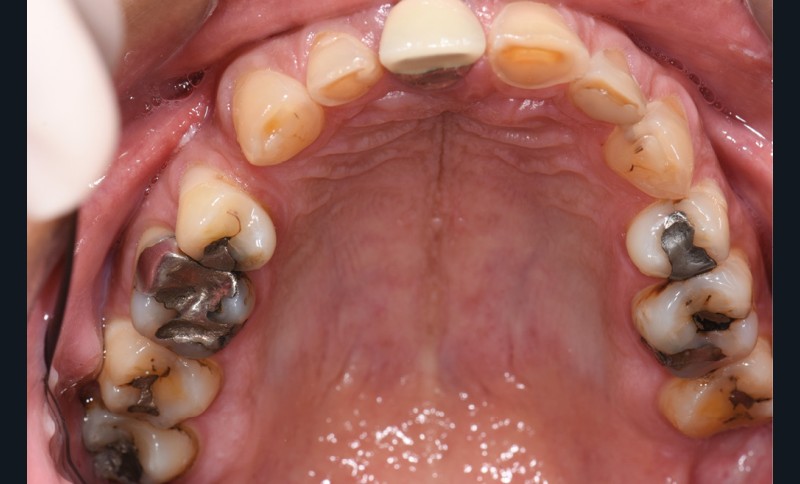

L’usure dentaire est de plus en plus fréquente au sein de nos cabinets. Nos patients y sont sujets de par leur alimentation parfois plus acide, leur mode de vie souvent plus stressant, et également une hygiène qui s’améliore et des dents qui vieillissent davantage.

L’étiologie de cette usure est multifactorielle, revêtant une composante de type attrition (usure par contact dento-

dentaire), une composante abrasive avec un brossage traumatique et, en dernier lieu, une légère composante tribo-érosive de par une pratique importante de sport avec gel et boisson acide (fig. 1-4) [1].